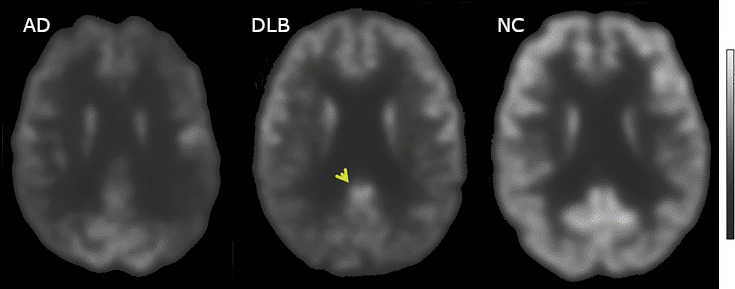

BRAIN IMAGING CT or MRI

MULTIPLE CORTICAL+SUBCORTICAL INFARCTS

ATROPHY of the BRAIN CORTEX

ALL THE THREE CONFIRM ISCHEMIA